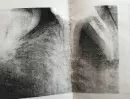

Вчера был на плановом осмотре у врача. Ничего не болело, и не болит. Года два назад перелечивал пульпит. Сегодня сделал снимок. Доктор сказал, что имеется обширная киста между корнями правой нижней 6-ки и нужно этот зуб удалять. На рентгене между корнями все черное. 7-го соседнего зуба нет уже лет 6, на 5-ке стоит коронка.

Да, между корнями зуба имеется разрежение костной ткани. Возможно два варианта, удаление зуба с последующим протезированием.